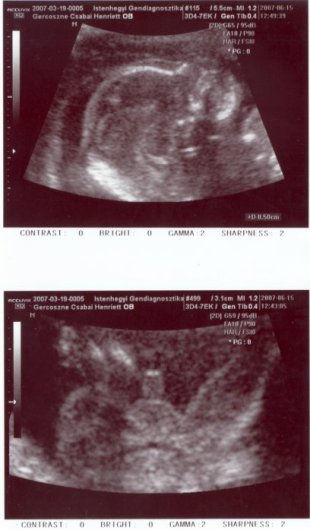

Teszek fel képet a Pici Csodamanóról

A felsőn a kis fejecske látható, ott mérték a nóziját, ami 5 mm...

A lenti, pedig magáért beszél...Ékes bizonyítéka, hogy Pici Fiúcska